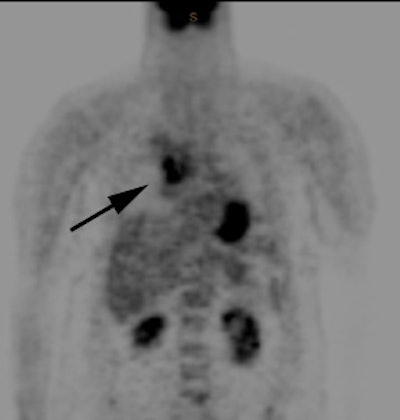

CT imaging confirmed a right upper lobe collapse with a central mass (white arrow). The lesion was hot on PET imaging (black arrow) and there was also uptake within pathologic mediastinal lymph nodes. The lesion proved to be a non-small cell lung cancer.  |